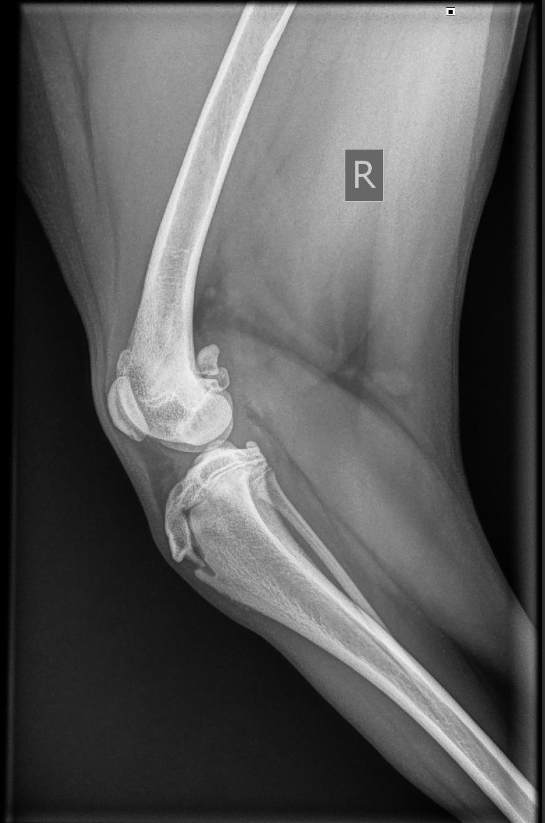

Doordat ik een second opinion wilde, ben ik uitgekomen bij een orthopedisch chirurg in Woerden. Daar ter plekke werd beoordeeld dat dit echt niet vanzelf goed zou komen, dat het om een behoorlijke patella luxatie gaat en dat een operatie noodzakelijk is om haar als actieve hond een goed leven te geven. Ook gaat de knieschijf er naar buiten toe uit en dat is ronduit uitzonderlijk te noemen. Zij wilden de operatie echter het liefst pas uitvoeren als de groeischijven van Pippa helemaal dicht waren. Op die manier is het maar 1 operatie in plaats van 2, want door de groei moet je immers anders nog een keer. (De foto hieronder is van november jl. waarin je dus nog open groeischijven kunt zien.) Al maanden loopt Pippa dus zoveel mogelijk rechte lijnen, speelt ze zo min mogelijk vrij met andere honden, loopt ze absoluut geen trappen en is springen eigenlijk niet de bedoeling (maar bij deze wilde gewoon niet tegen te houden). We moeten de slijtage aan de knie daarmee zoveel mogelijk beperken.